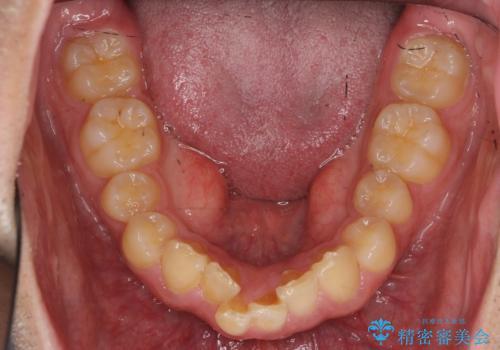

出っ歯を治したい 深いかみあわせ インビザラインで治療

下顎は歯列を拡大して並べました。

矯正前に下顎の骨隆起の切除をご希望により行っています。(Dr.大元執刀)

また、過蓋咬合(深いかみ合わせ)で食いしばりがきつく、歯の移動には大変時間がかかりました。